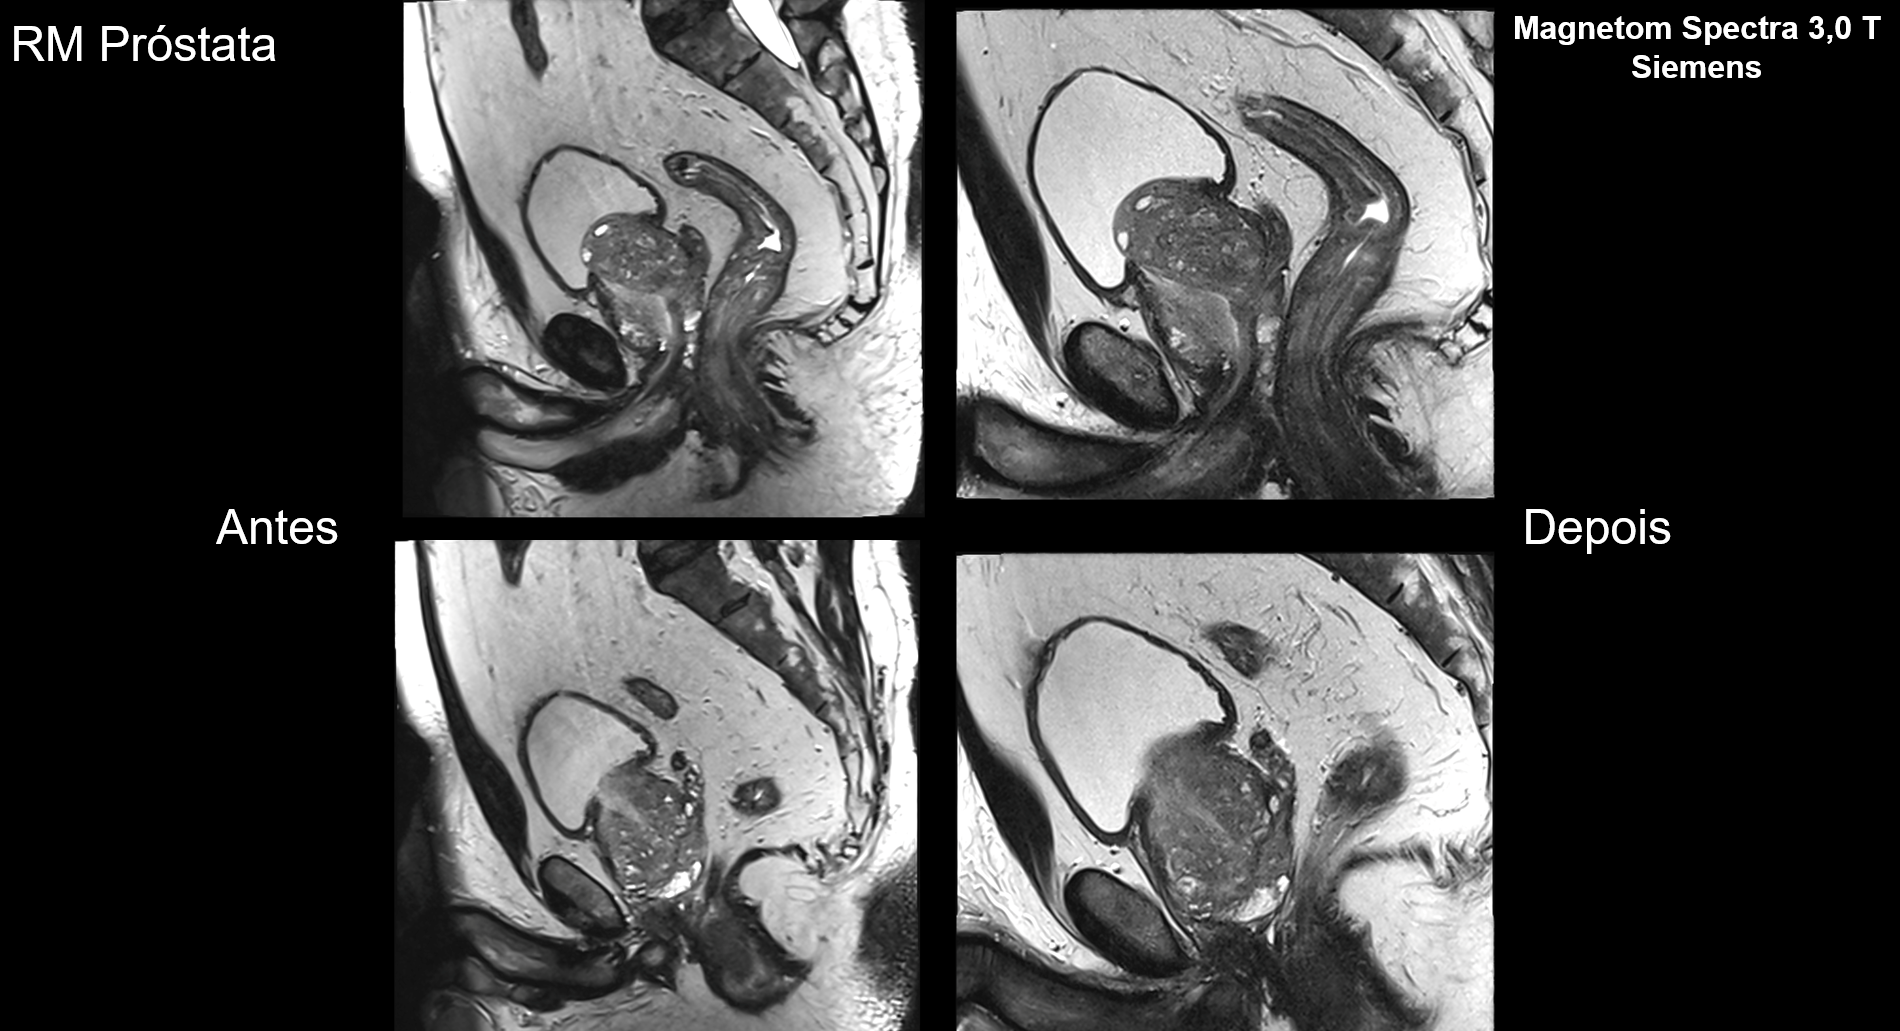

Melhorias implementadas em alguns exames, comparando antes e depois.